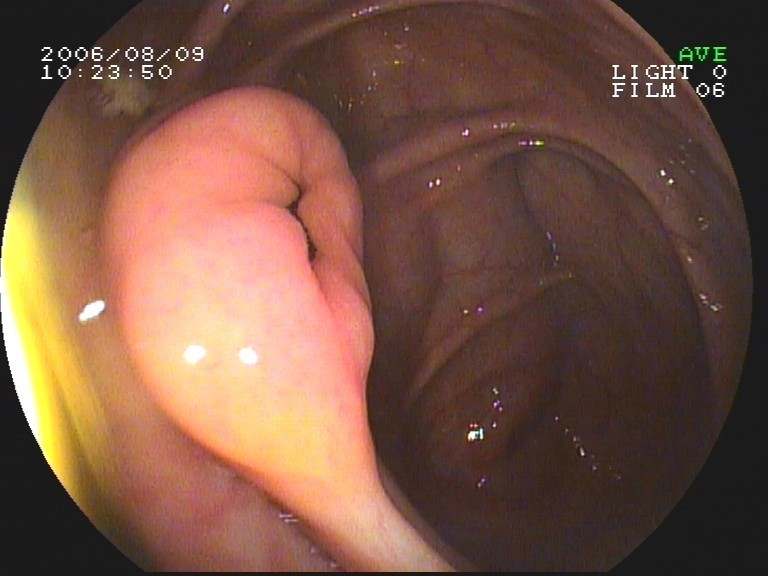

Coloskopie - langgestielter Dickdarmpolyp (Adenom)